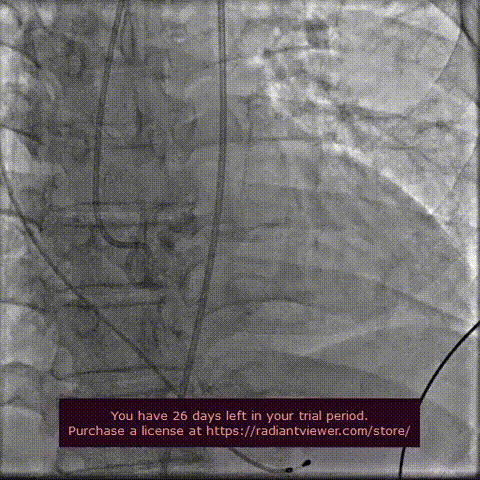

瓣膜定位释放:

瓣膜初定位

瓣膜稳定释放

工作位造影

工作位造影2

瓣膜稳定脱钩

瓣膜释放后主动脉根部造影:瓣膜释放后形态位置良好,造影无反流。